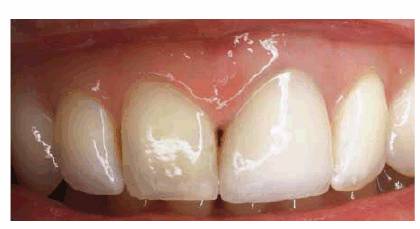

The most practical restorative treatment to eliminate a

small diastema between sound teeth is by direct bonding with composite resin (Figures 23-12A and B, 23-12C, 23-12D, 23-12E, 23-12F, 23-12G and H). Direct composite resin bonding is fast (one

Figure 23-12A and B: The most practical method for closing a simple diastema is with composite resin bonding.